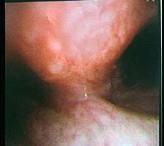

65岁男性,咳嗽、胸痛半年,支气管镜如图,可能的诊断是 ( )A.肺结核B.肉芽肿C.支气管内膜结核D.错构瘤E.气管癌

问题 65岁男性,咳嗽、胸痛半年,支气管镜如图,可能的诊断是 ( )

选项 A.肺结核 B.肉芽肿 C.支气管内膜结核 D.错构瘤 E.气管癌

答案 E